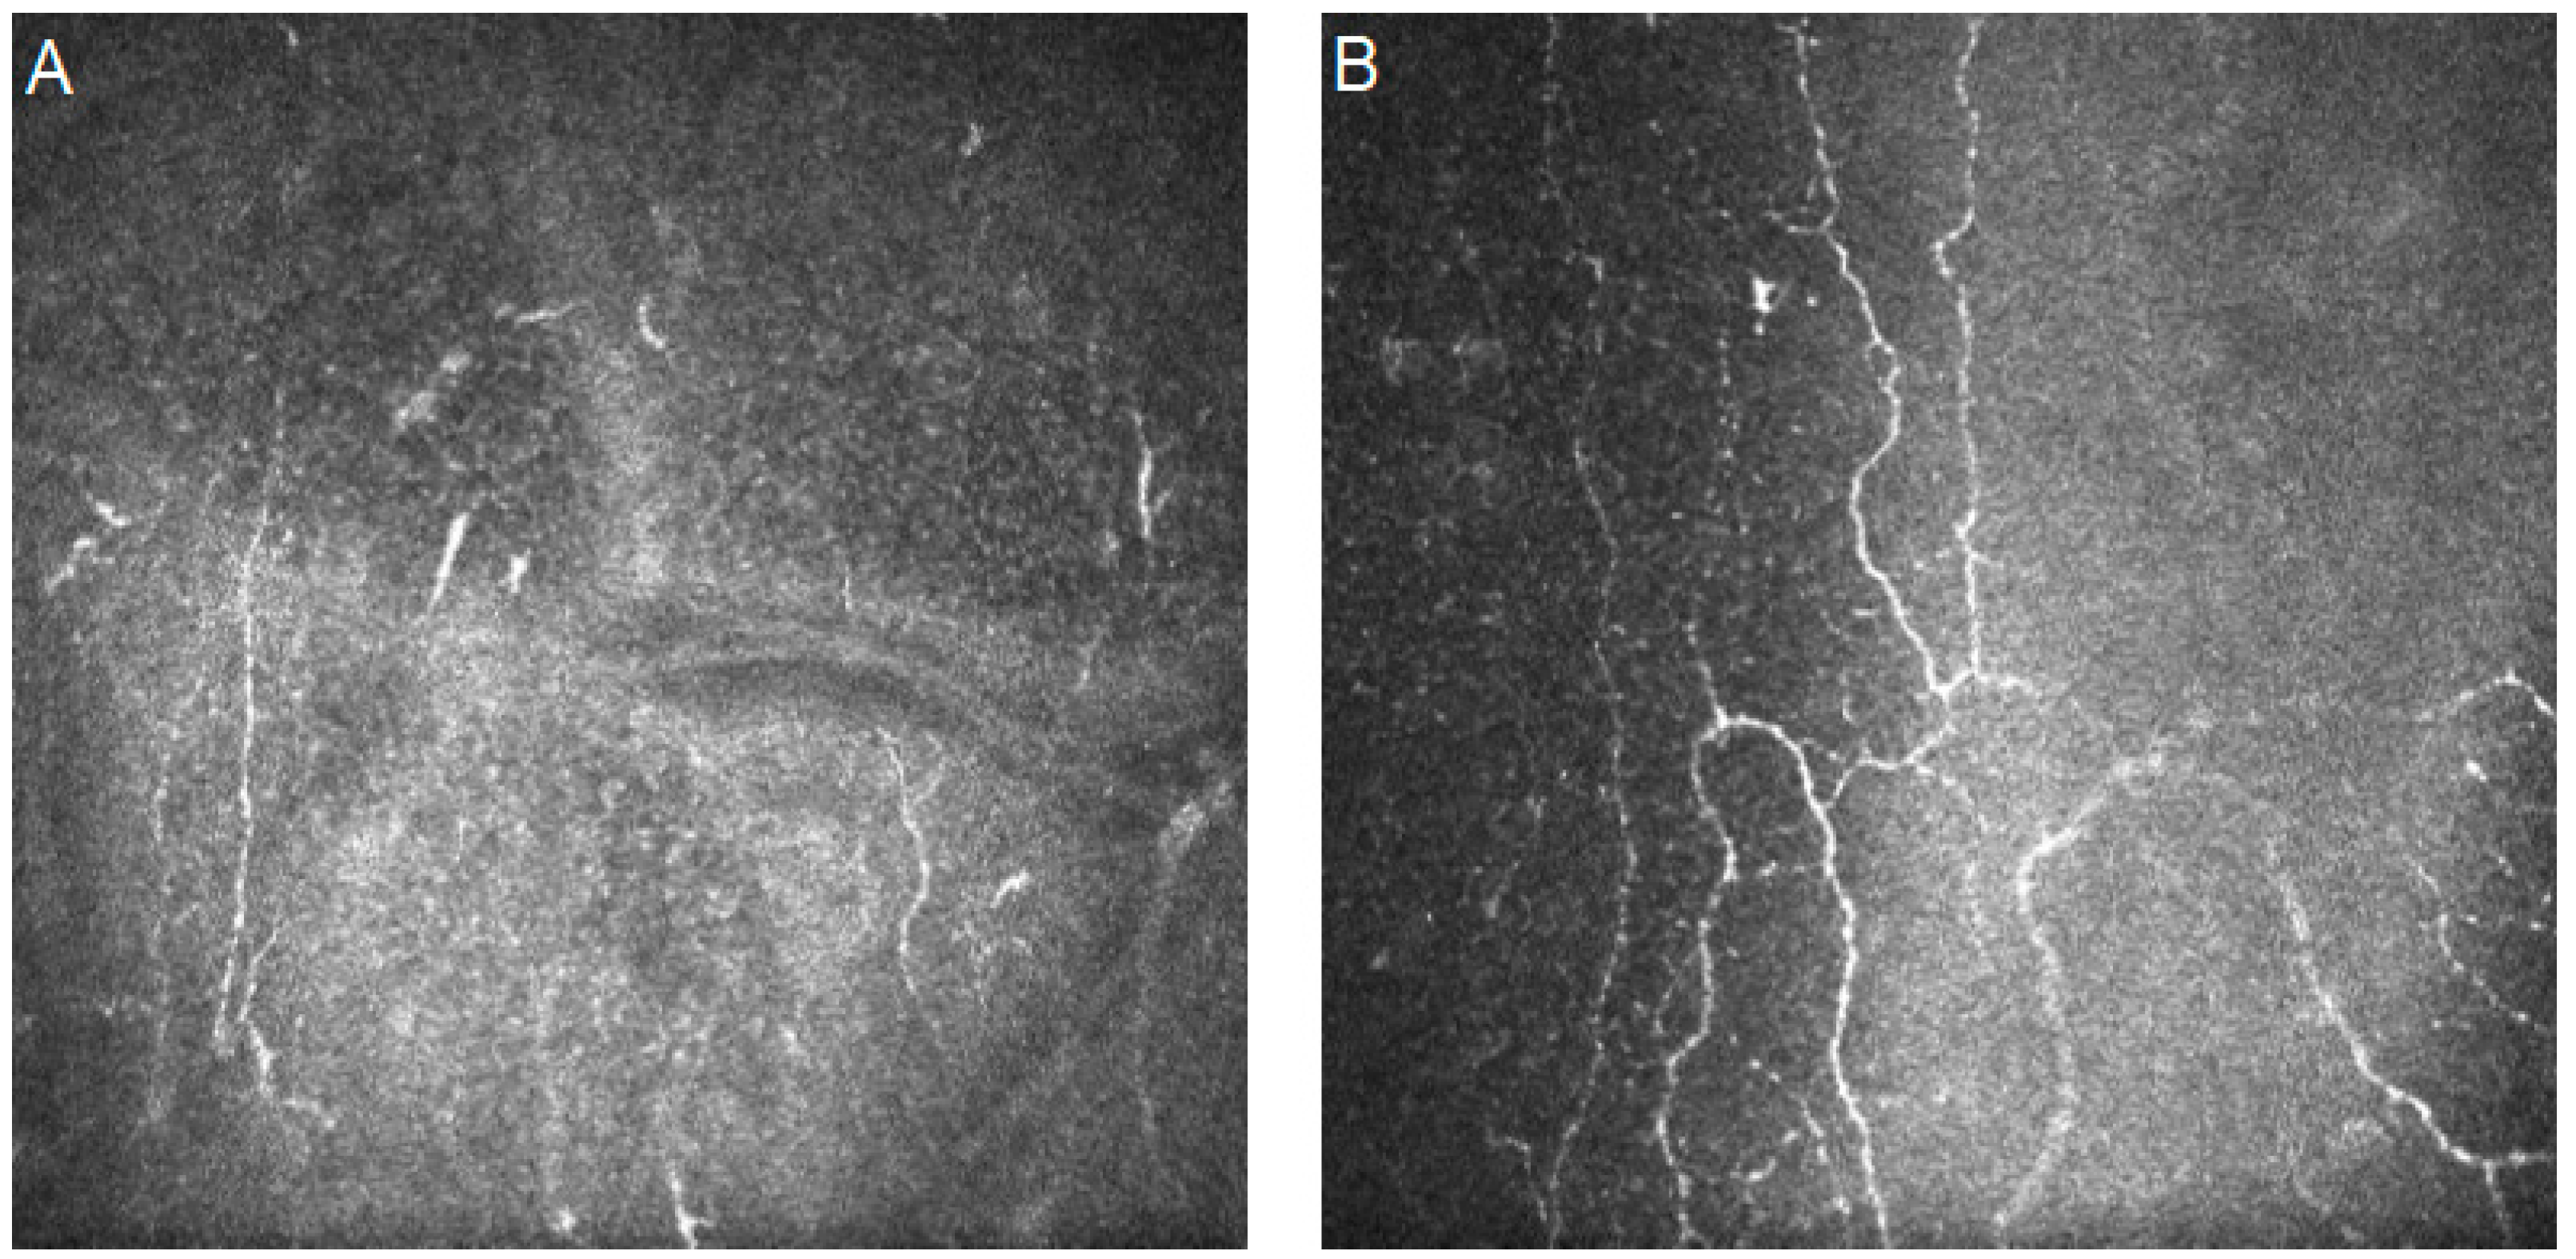

- Wei, S.; Shi, F.; Wang, Y.; Chou, Y.; Li, X. A Deep Learning Model for Automated Sub-Basal Corneal Nerve Segmentation and Evaluation Using In Vivo Confocal Microscopy. Transl. Vis. Sci. Technol. 2020, 9, 32. [Google Scholar] [CrossRef]

- Jing, D.; Liu, Y.; Chou, Y.; Jiang, X.; Ren, X.; Yang, L.; Su, J.; Li, X. Change patterns in the corneal sub-basal nerve and corneal aberrations in patients with dry eye disease: An artificial intelligence analysis. Exp. Eye Res. 2021, 215, 108851. [Google Scholar] [CrossRef]